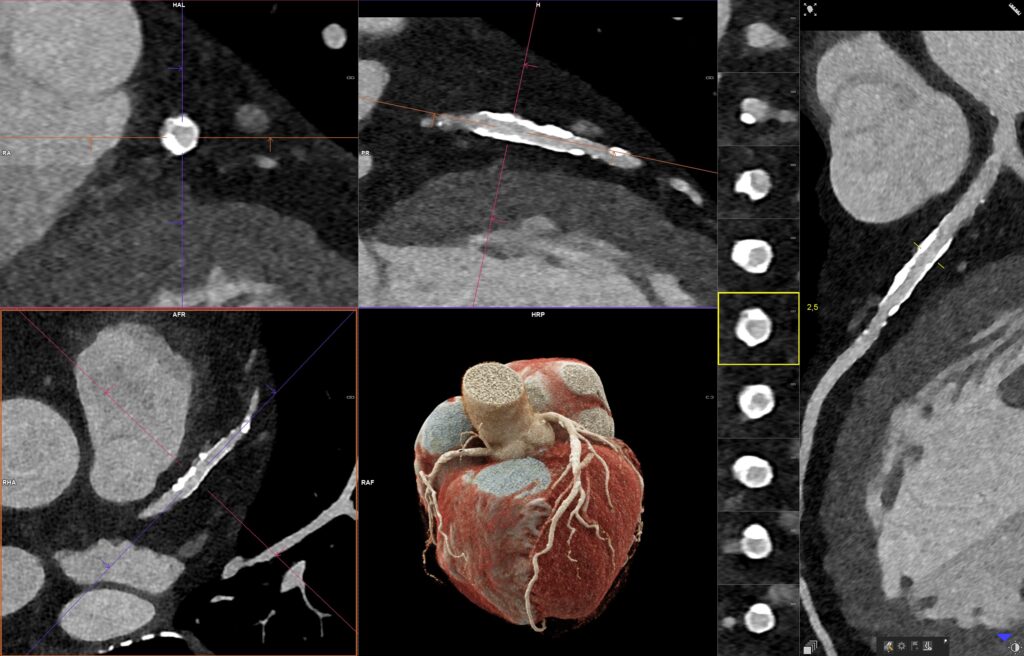

Bei Verdacht auf eine Erkrankung des Herzens oder der Herzkranzgefäße ist oft eine Herzkatheter-Untersuchung das Mittel der Wahl. Eine schonendere Möglichkeit, um eine Herzkrankheit ebenso präzise und verlässlich zu diagnostizieren, ist u.a. ein „Stress-MRT“ des Herzens. Dabei handelt es sich um eine spezielle Form der kardialen Magnetresonanztomographie, bei der das Herz unter (medikamentös initiierter) Belastung untersucht wird. Der ab sofort im Diagnostikzentrum Graz (DZG) verfügbare Magnetresonanztomograph „MAGNETOM Sola Cardiovascular Edition“ ermöglicht diese „Stress-Diagnose“. „Ein Stress-MRT zeigt, wie gut der Herzmuskel unter Belastung durchblutet wird. Das erlaubt eine klarere Identifizierung einer wirksamen Koronarstenose und die Beurteilung, ob statt einer Operation nicht auch eine medikamentöse Behandlung das Mittel der Wahl ist“, so Univ.-Doz. Dr. Peter Kullnig, Gründer und ärztlicher Leiter des DZG. Mit der Inbetriebnahme des neues High-Tech-Gerätes sind im DZG sowohl quantenzählende Computertomographen als auch der beschriebene Magnetresonanztomograph im Einsatz – eine Kombination, die, wenn angezeigt, eine bisher nicht gekannte Diagnosetiefe für Patienten ermöglicht.

Pro vermiedenem, unnötigem Katheter spart das Gesundheitssystem rund 70 % bis 80 % der Kosten. Hochgerechnet auf die ca. 26.000 gesetzten Stents pro Jahr in Österreich ergibt sich daraus eine Einsparung in Millionenhöhe. „In Sachen Herzdiagnostik haben wir damit ein neues Level erreicht. Mehr als 20.000 Herzuntersuchungen in den letzten Jahren machen Graz zur ,Herz-Hauptstadt` im DACH-Raum. Dank unserer zwei photonenzählenden Computertomographen NAEOTOM Alpha.Peak und dem neuen MRT ab März können sich tausende Patienten aus der Steiermark einen invasiven Herzkatheter ersparen“, so Kullnig.